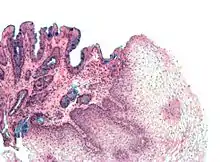

The mucosal layer consists of a epithelial layer, and its underlying supportive tissue, the Lamina Propria. It is separated from the submucosal layer by the Muscularis Mucosa. The epithelial layer varies from section to section of the gut. In the oesophagus it is a non-cornified stratified squamous epithelium; in the stomach it is mainly mucosal cells; the small intestine and large intestine are characterized by absorptive cells, with many mucous producing goblet cells. In the absorptive sections of the intestine, the surface are for absorption is greatly increased by finger-like projections into the lumen called villi, and the absorptive cells themselves also have small projections of microvilli, giving them the appearence of a brush border when viewed with a light microscope.

The basic layout pattern holds true in the stomach, although the stomach has a third inner layer of oblique muscle fibers. The mucosal layer has numerous pits opening into the lumen, the mouths of the gastric glands. Some of these glands penetrate down into the submucosal layer.

Gastric Glands

The gastric glands secrete mucous, hydrochloric acid and enzymes into the stomach. They are located for the most part in the mucosal layer of the stomach, but some of the deeper gland penetrate into the submucosal layer, and secrete into the lumen via ducts. Several different secretory cells are found: mucous; parietal; chief cells; D cells; enterochafin cells; and G cells.

Mucous cells secrete both mucous and bicarbonate, substances that protect the stomach from auto-digestion. Parietal cells secrete hydrochloric acid (1-3 liters a day) which cause the pH in the stomach to fall as low as 1. Chief cells secrete the enzyme pepsinogen, which is activated to pepsin by the pH of the stomach. G cells produce gastrin, a hormone that promotes gastric acid secretions and stimulates the growth of the gastric mucosa.

![]() |

| Cardiac glands (at cardia) | Pyloric glands (at pylorus) | Fundic glands

(at fundus) |

The composition of the gastric glands varies throughout the stomach. In the fundus, the glands are more branched and contain all the different kinds of secretory cells. In the pyloric part of the stomach the glands are deeper and contain more mucous cells. Chief cells are found only in the fundus of the stomach, G cells are found mainly in the antrum, and the other cells are found in all areas.